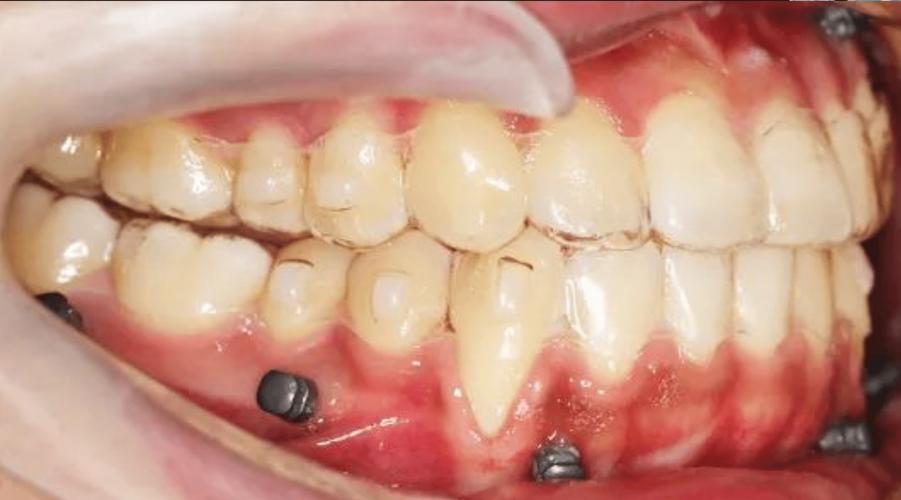

(图片来源网络,侵删)经验丰富的种植医生会综合考虑所有因素(骨量、位置、咬合力、患者期望等),选择最适合该患者个体情况的种植体长度和直径,以达到最佳的长期效果和成功率。